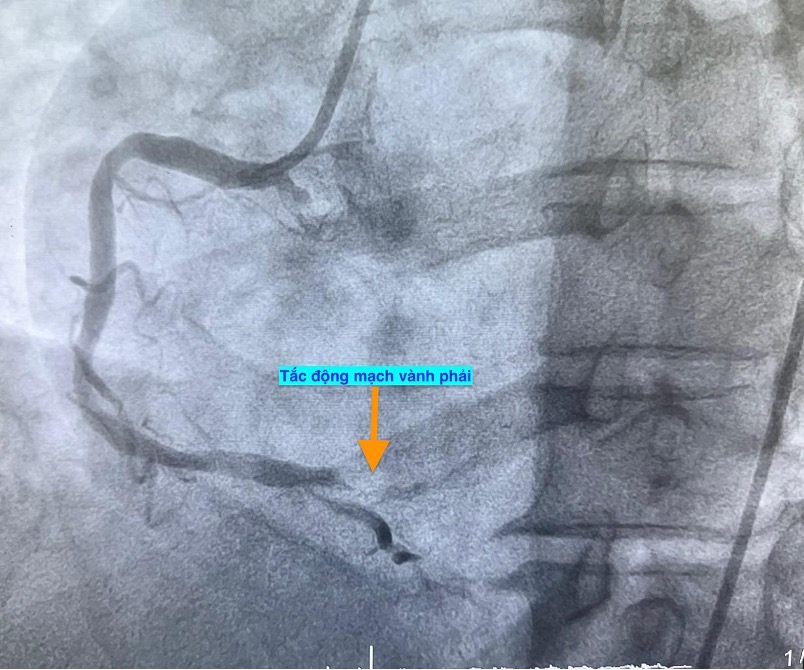

Trường hợp thứ hai, lúc 9 giờ 5 phút, nam bệnh nhân 53 tuổi nhập viện vì chóng mặt và nóng rát thượng vị. Điện tâm đồ ghi nhận nhồi máu cơ tim cấp vùng dưới. Kết quả chụp mạch vành xác định bệnh nhân cũng bị tắc động mạch vành phải.

Trường hợp thứ ba, lúc 15 giờ 53 phút, nam bệnh nhân 78 tuổi nhập viện vì đau ngực. Bệnh nhân cho biết đau ngực từng cơn trong 3 ngày, ngày nhập viện thì đau ngực liên tục. Điện tim gợi ý nhồi máu cơ tim cấp; chụp mạch vành cấp cứu phát hiện bệnh nhân cũng tắc động mạch vành phải.

Hình ảnh chụp mạch vành cho thấy các bệnh nhân bị tắc mạch máu tim (do mảng xơ vữa, huyết khối) dẫn đến tình trạng thiếu máu cục bộ và nhồi máu cơ tim cấp